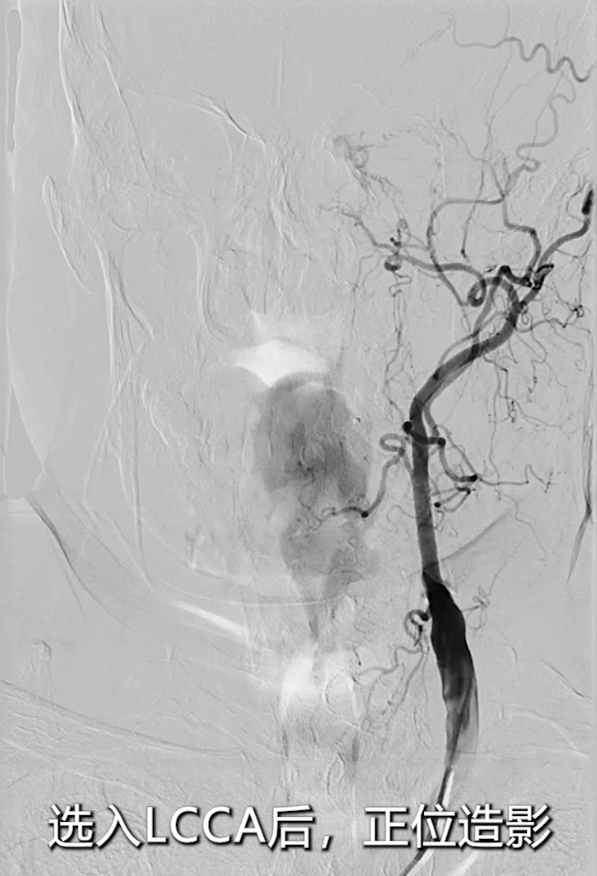

左侧颈总动脉造影:明确左侧颈内动脉闭塞,侧支循环通过颈外动脉部分供应颅内血流;

右侧颈总动脉造影(正位、汤氏位、侧位):明确右侧颈内动脉重度狭窄,病变远端直径5mm、近端直径8mm,长度约30mm,远端锚定区条件理想。